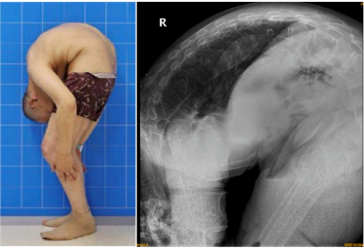

风华正茂时因为患上最严重的强直性脊柱炎,成了「3-on折叠人」,不能直

12月13日,46岁的"折叠人"李华终于可以和正常人一样,与治疗他的医护

到了30岁,李华的 整个上半身开始逐渐弯曲.